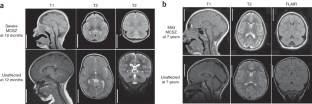

Maintenance of DNA integrity is crucial for all cell types, but neurons are particularly sensitive to mutations in DNA repair genes, which lead to both abnormal development and neurodegeneration1. We describe a previously unknown autosomal recessive disease characterized by microcephaly, early-onset, intractable seizures and developmental delay (denoted MCSZ). Using genome-wide linkage analysis in consanguineous families, we mapped the disease locus to chromosome 19q13.33 and identified multiple mutations in PNKP (polynucleotide kinase 3′-phosphatase) that result in severe neurological disease; in contrast, a splicing mutation is associated with more moderate symptoms. Unexpectedly, although the cells of individuals carrying this mutation are sensitive to radiation and other DNA-damaging agents, no such individual has yet developed cancer or immunodeficiency. Unlike other DNA repair defects that affect humans, PNKP mutations universally cause severe seizures. The neurological abnormalities in individuals with MCSZ may reflect a role for PNKP in several DNA repair pathways.

J.S. helped to characterize MCSZ syndrome, identified the MCSZ locus and calculated lod scores, sequenced genes in the MCSZ locus to identify PNKP mutations and wrote the manuscript; E.C.G. helped to characterize MCSZ syndrome, identified the moderately affected MCSZ family, performed RT-PCR on moderately affected family samples, performed comet assays, organized and analyzed Sequenom experiments, did analysis of PNKP mutation, performed mouse RNAi experiments, helped perform mouse in situ hybridizations and wrote the manuscript; C.A.M. sequenced genes in the MCSZ locus to identify PNKP mutations and helped perform human in situ hybridizations; M.H. identified affected patients and provided clinical information; J.J.R. performed PNKP protein blots and confirmatory comet assays; W.E. identified affected patients and provided clinical information; A.B. organized clinical information and patient samples; B.B. organized clinical information and patient samples; D.G. organized patient samples and helped perform Sequenom experiments; K.A. organized patient samples and helped perform sequencing experiments; V.S.G. helped analyze Sequenom experiments; B.S.C. helped organize clinical information to identify MCSZ syndrome; A.G. identified affected patients and provided clinical information; R.S.H. helped organize genetic data and calculate lod scores; M.T. identified affected patients and provided clinical information; K.W.C. advised on comet assays, supervised PNKP protein blotting and edited the manuscript; A.J.B. characterized MRIs for patient classification; C.A.W. directed the overall research and wrote the manuscript.